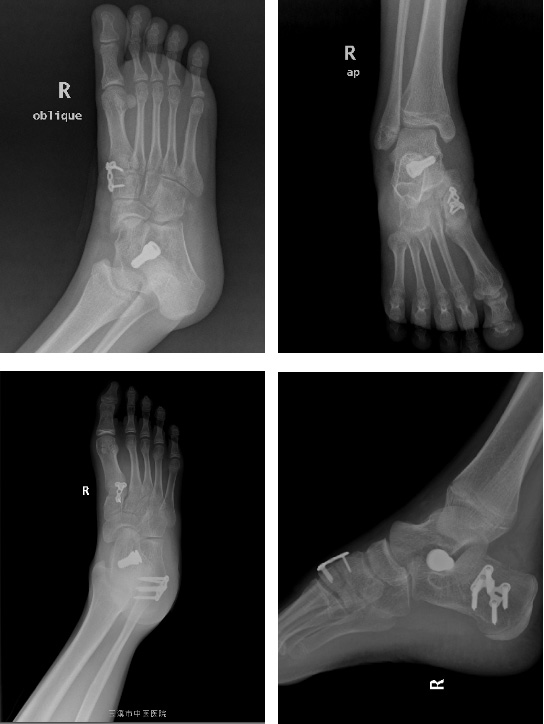

5. 經(jīng)過(guò)上述保守治療,若患兒癥狀改善不明顯,可行手術(shù)治療,以矯正平足從而緩解癥狀。